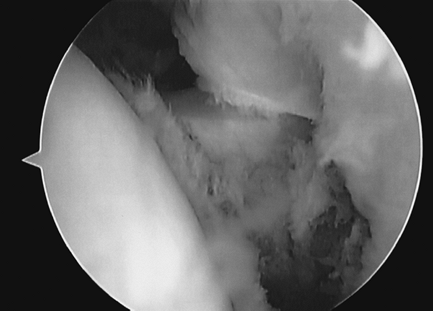

The initial phase (“freezing phase”) is

active and passive motion. Arthroscopy and histology studies

demonstrate acute synovitis (Fig. 46-1). -

Figure 46-1 Joint synovitis encountered at arthroscopy.